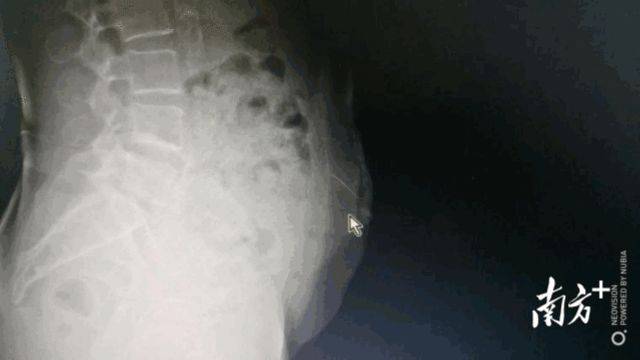

影像显示阿婆断针的位置在家自行针灸出意外67岁阿婆针断腹中67岁的梁阿婆在年轻时曾当过几年“赤脚医生” 。 在工作中 , 她接触到针灸这一传统疗法 。 因曾针灸帮助患者缓解症状 , 阿婆从此深信针灸的功效 , 甚至在过去的数十年里 , 多次自行给自己和家人进行针灸 。 前段时间 , 阿婆因糖尿病致右下腹壁软组织感染 , 出院后仍时常感觉感染部位疼痛 , 于是就想起了自己信赖的针灸疗法 , 希望通过给自己针灸来减缓疼痛 。 但这次的针灸却不像往日一般顺利 。 7月23日 , 当梁阿婆在家中再次给自己针灸时 , 不曾料想针断在了腹中 。 此后 , 梁阿婆又尝试自己切开扎针的位置 , 想把断针取出 , 却无果 。 之后 , 阿婆感觉腹部疼痛愈发难忍 , 紧急来到广医三院就医 。

三维重建显示阿婆断针的位置体内断针风险大医生CT定位、手术取针入院后 , 医生第一时间通过拍片发现 , 针还在梁阿婆腹壁里 。 而该针又细又长 , 稍有不慎就可能扎到腹腔内脏器 , 带来严重危害 。 “由于腹壁是运动的 , 患者弯腰、转身等动作都可能导致锋利的针深入游走 , 插到内脏导致肠穿孔 , 甚至扎到腹壁下动脉导致血管大出血 。 同时 , 在家自行针灸 , 所用的针未必经过了严格消毒程序 , 若不及时取出有可能导致深部软组织感染和破伤风 。 ”广医三院肝胆外科副主任医师潘裕国说 , 留在体内的针此刻就像一枚定时炸弹 , 随时会给患者带来生命危险 。 为了确认针的位置 , 尽快把针取出 , 潘裕国对患者做了CT定位和三维重建 , 发现针已从皮下组织扎到了腹直肌里 , 万幸未伤及内脏 。 潘裕国迅速为梁阿婆安排介入手术 。 最终 , 医生通过垂直面向下切开2厘米 , 成功将针从腹中取出 。 此外 , 医院还给梁阿婆打了破伤风针 , 避免感染风险 。 但由于针扎的位置就在包块处 , 阿婆的感染可能要面临更久的愈合期 。